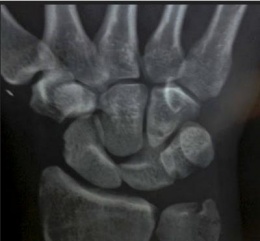

Deben realizarse exámenes radiográficos en vistas lateral y anteroposterior. La vista lateral es la de más valor, pues en ella se observa la medialuna típica del hueso rotado hacia la región palmar y sin la articulación propia del hueso grande. En la vista anteroposterior, la imagen rectanguar normal del semilunar se vuelve triangular por la luxación.